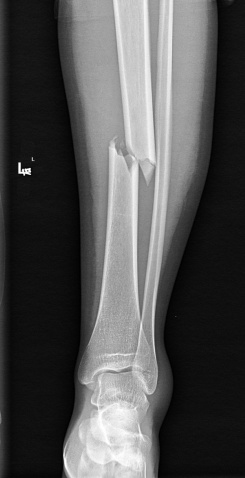

首先,平片作为放射检查中最便捷便宜的检查方式,医生会要求患者先去拍个平片,达到筛查、排除、诊断的目的。例如骨折、肺部、心脏、腹部和盆腔病变等疾病,尤其是突发急性疼痛或是难以控制的慢性疼痛,普通X线检查速度较快,不会延误治疗。通常,X线是骨折检查的首选,明显的骨折X线就可以明确诊断,简便易行,费用低。比如下图中,通过平片诊断这位外伤病人为左侧胫骨中段骨折并移位,是很明确的。

(平片)